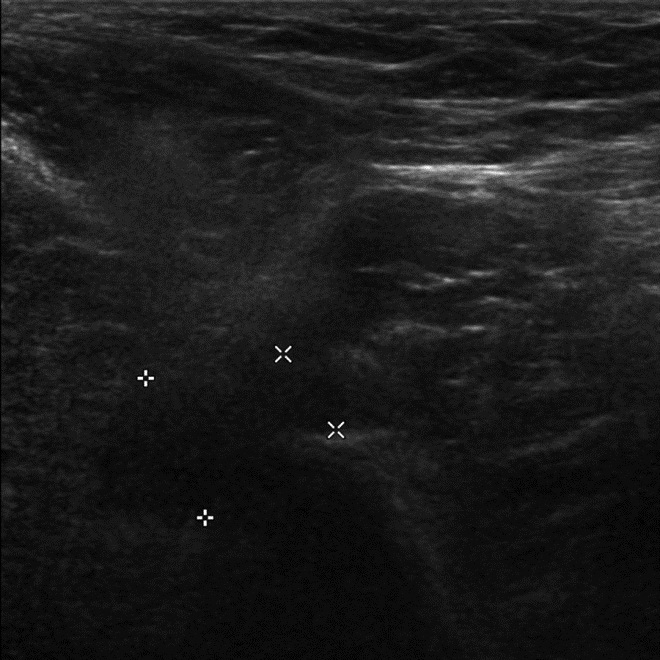

This technique can be used to evaluate for pseudotumor in metal-on-metal implants with rapid assessment of anterior, posterior, and lateral aspects of the hip to identify heterogeneous, hypoechoic masses with no or minimal intralesional vascularity on Doppler ultrasound (Figure 27) (Chen, 2011). It is also useful for evaluation of the rotator cuff in patients with prior cuff repair or proximal humerus fracture fixation (Figure 28), as well as for assessment of ankle tendons in patients with persistent pain following fracture fixation.